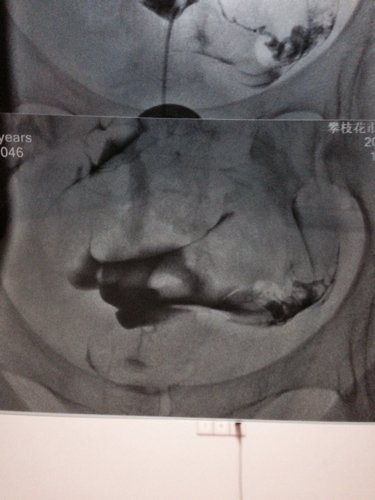

请医生帮忙看看我的输卵管造影图片,有一边是通而不畅还是不通 谢谢

病情分析: 你好,从你的左右骗子来看,左侧输卵管应该是通畅的;而右侧输卵管在子宫角处,也就是与子宫相交接的部位都没有显影,考虑是输卵管的间质部梗阻不通。子宫腔形态呈倒三角形,正常。 指导意见: 建议:可以做B超监测卵泡的发育和排卵情况,如果是左侧卵巢有优势卵泡并排卵的话,那就应该在排卵日前后安排同房...,好样的几率就会很高。如果是右侧卵巢排卵的话,由于右侧输卵管的梗阻不通,一般不会怀孕。